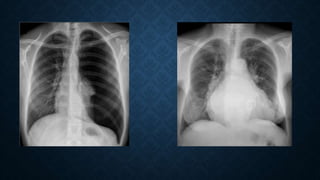

Thoracic Aortic Aneurysm Tubular heart in COPD.

Also, notice the hyperinflated

lung and lowered down

diaphragm.